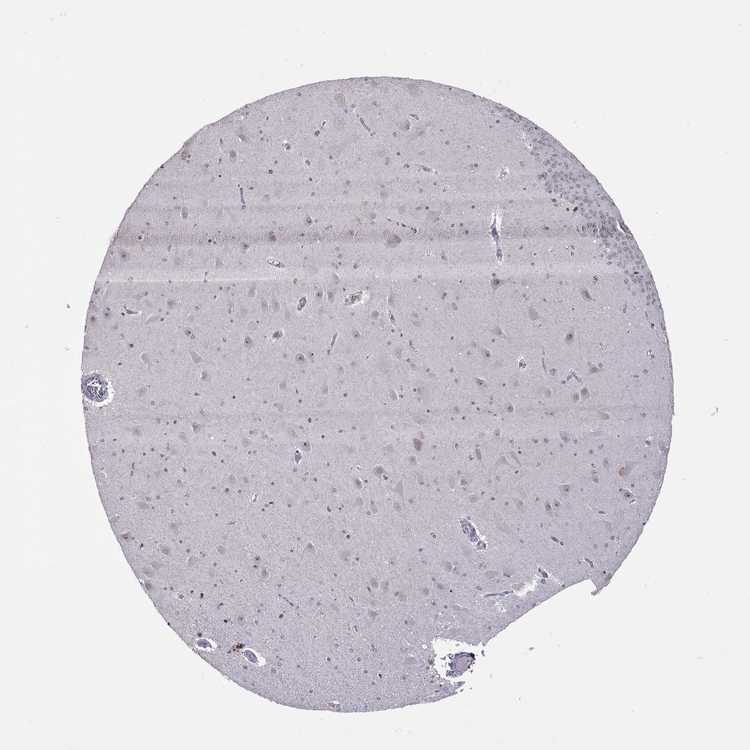

HIPPOCAMPUS - Antibody stainingi

Antibody staining in the annotated cell types in the current human tissue is reported as not detected, low, medium, or high, based on conventional immunohistochemistry profiling in selected tissues. This score is based on the combination of the staining intensity and fraction of stained cells.

Each image is clickable and will lead to virtual microscopy that enables deeper exploration of all samples and also displays staining intensity scores, fraction scores and subcellular localization as well as patient and tissue information for each sample.

Antibody HPA077434

Glial cells Not detected

Neuronal cells Low